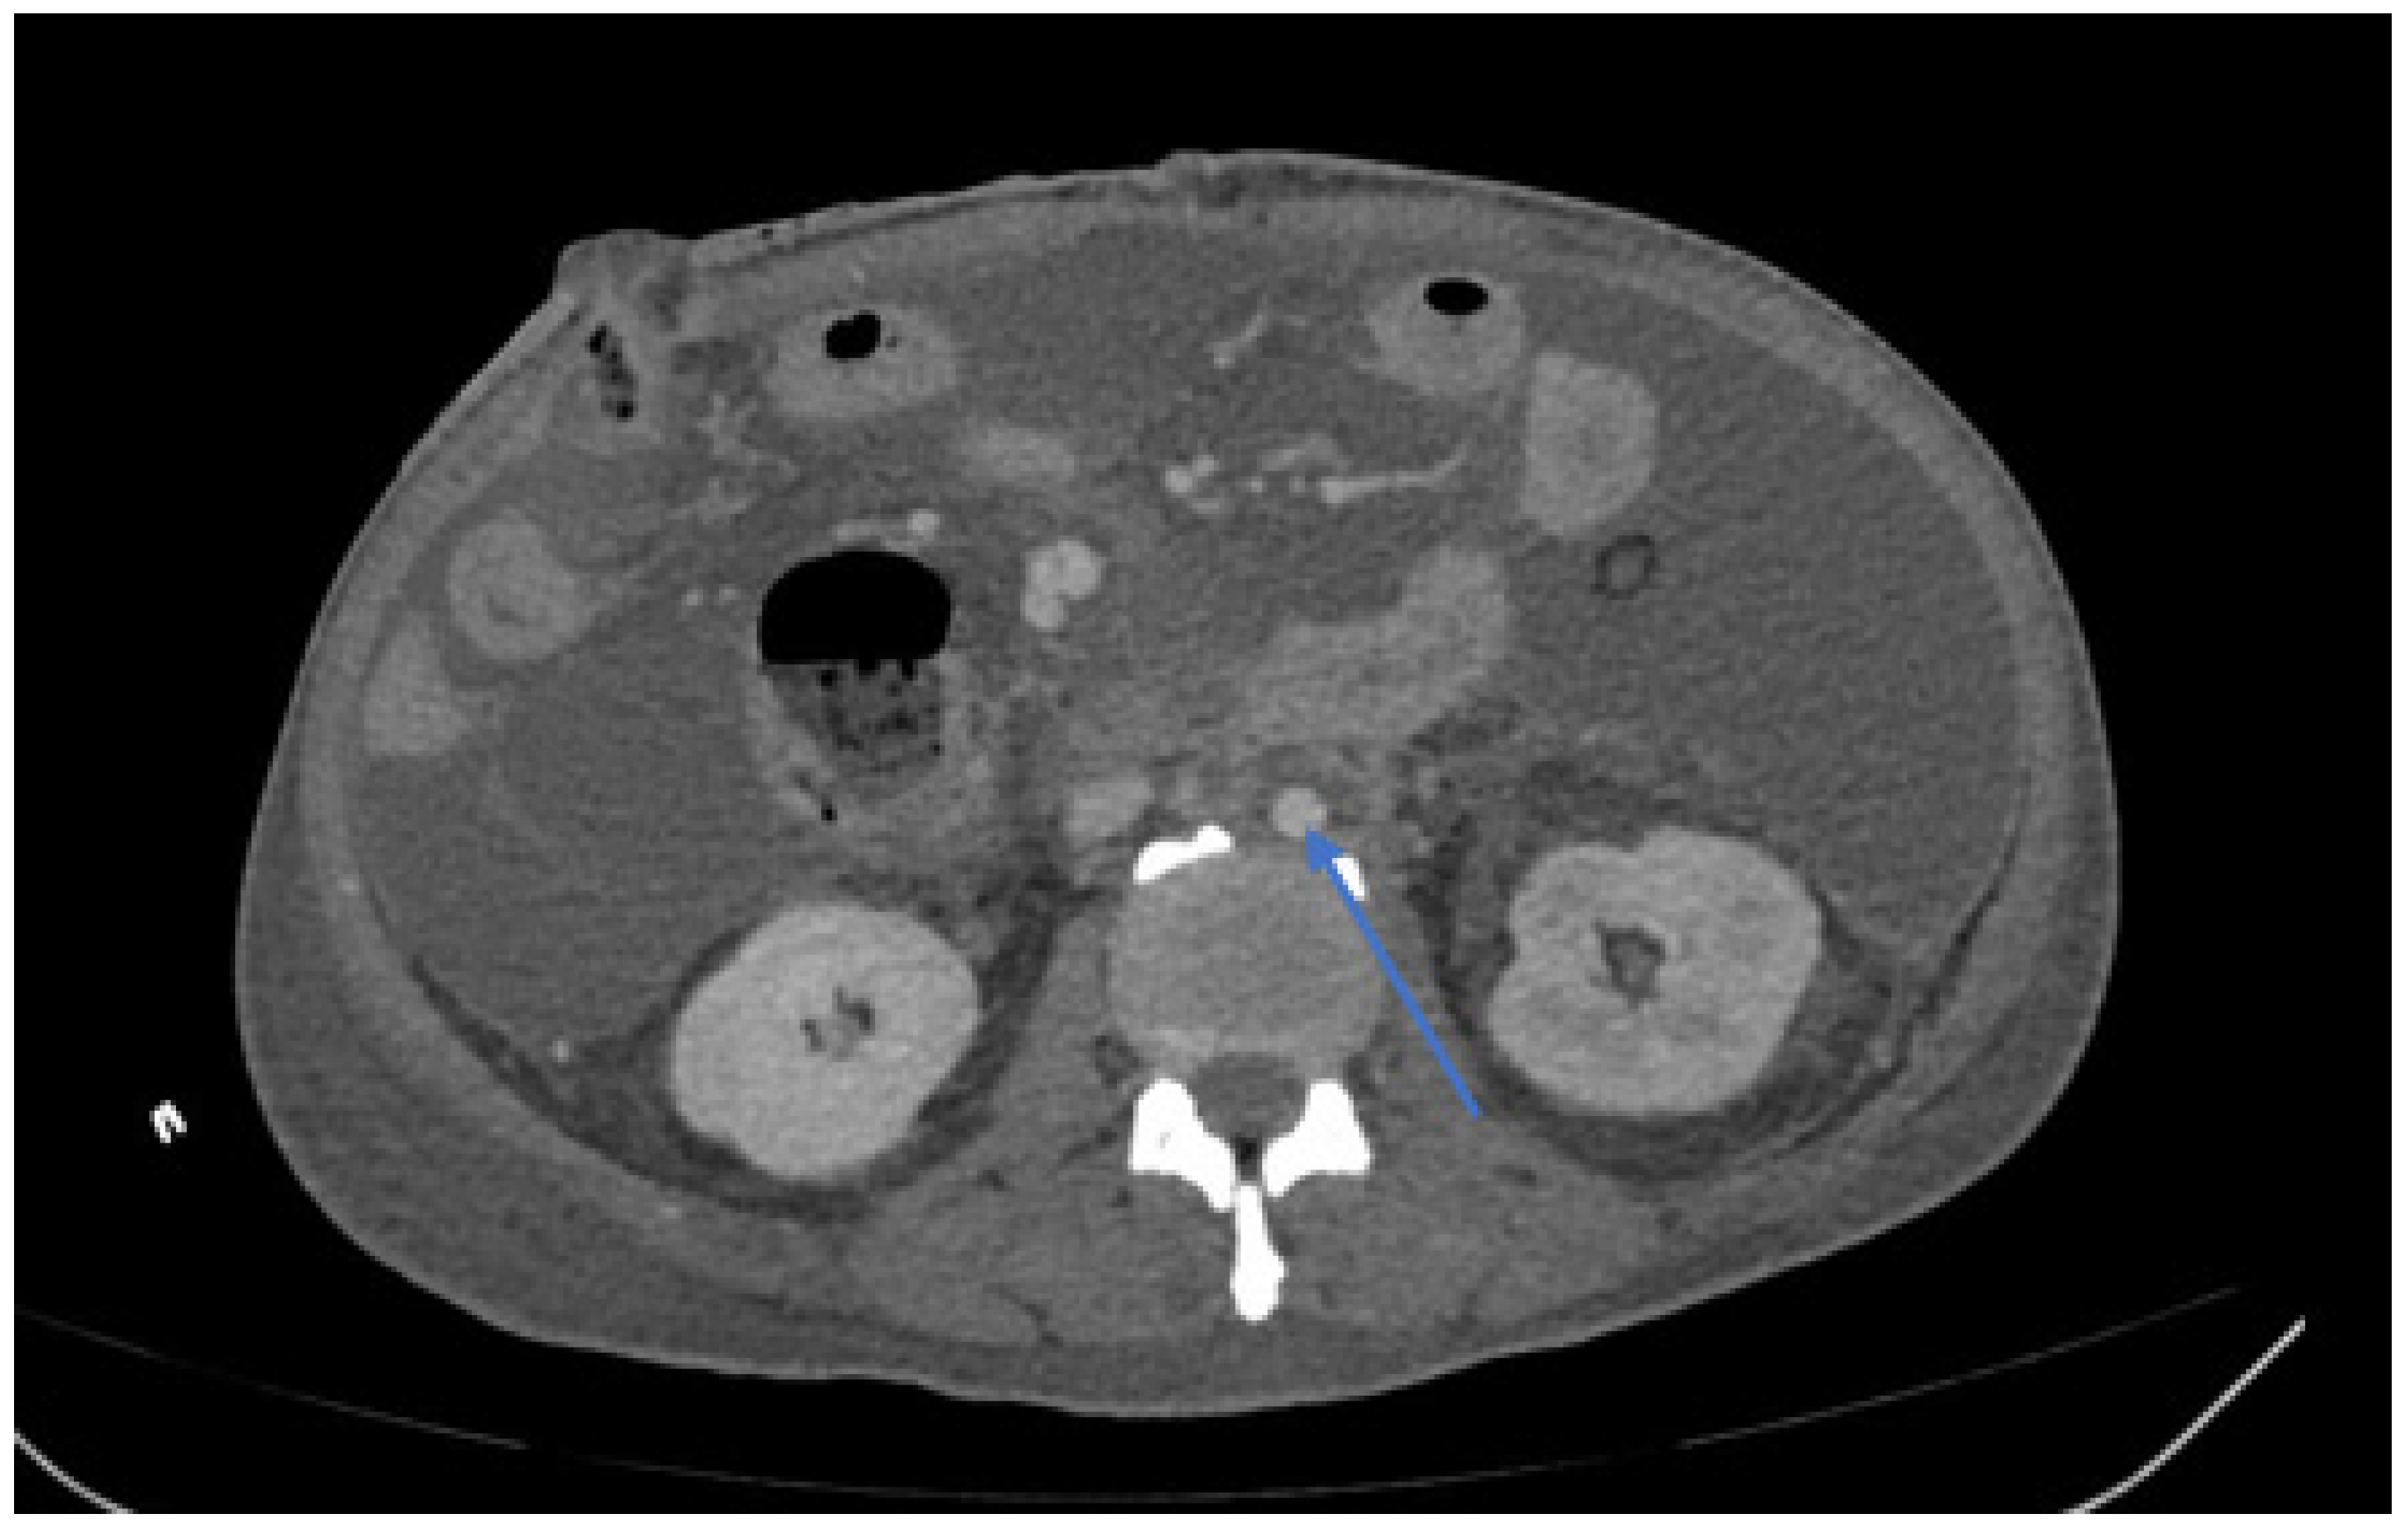

| Peri-graft/retroperitoneal abscess | 21 (48%) |

| Graft duodenal fistula | 10 (23%) |